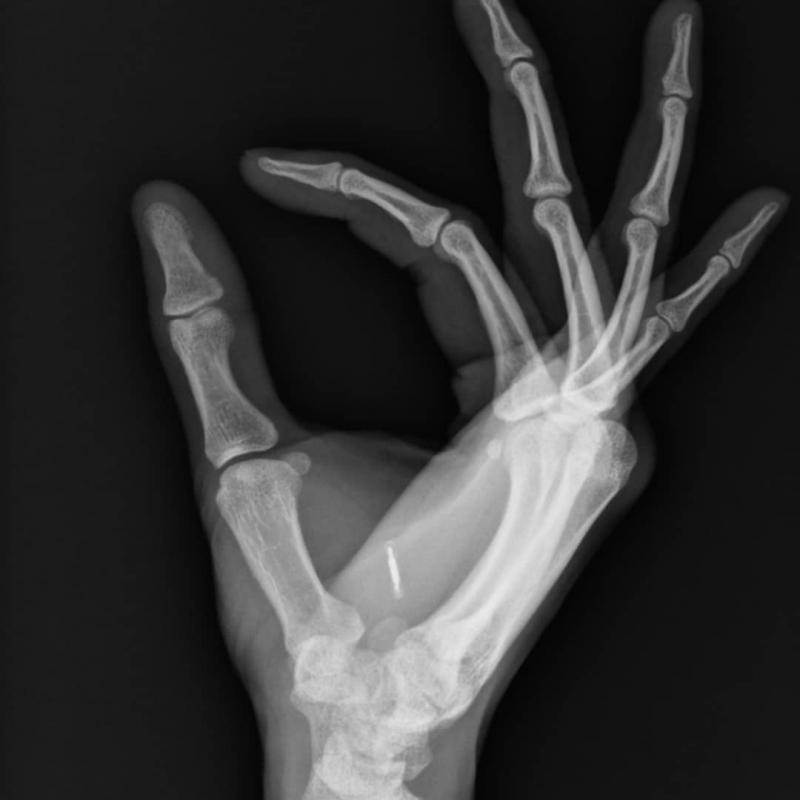

這種在手掌虎口處植入的晶片取代了電子錢包,人們不需要隨身攜帶銀行卡、鑰匙卡等等,只要用手輕輕觸摸晶片,就能成功付款、開門、打卡。晶片和手術只要180美元(約台幣5,500元),這個價格比想像中便宜很多。

▼有些公司主動向員工提供這項服務,讓員工用手掌中的晶片來打卡。有些人擔心安全問題,其實沒有必要,因為這款晶片沒有GPS功能,無法用它來跟蹤人員,也無法靠它來看到其他人的位置。

有人擔心晶片儲存太多個人資訊,有資安危機。研究人員解釋說,這款晶片只有在距離感應器幾公分的地方才能發揮功能,一般情況下個人資訊不會被竊取。晶片植入手掌中後看起來並不明顯,也不會影響活動。